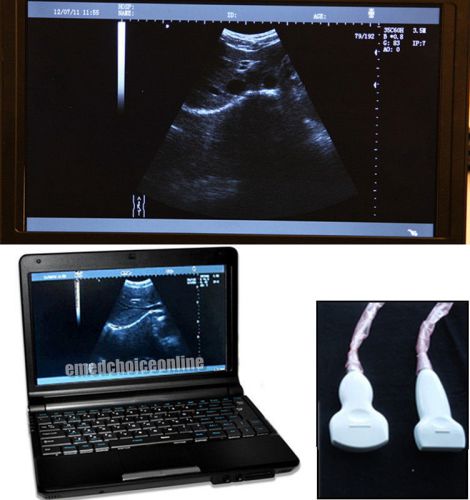

10.1' Digital Laptop Ultrasound Scanner Convex & Linear 2 Probes + 3D Free SHIP

Digital Portable Ultrasound Scanner + 3.5MHz CONVEX probe + free 3D software BES

NEW Full Digital Laptop Ultrasound Scanner Machine + Convex + Trans-vaginal + 3D

Digital Laptop Ultrasound Scanner Portable BOX Convex Probe+2014NEW FREE 3D VGA

3D Portable Digital Ultrasound machine Scanner system Trans vaginal probe FDA